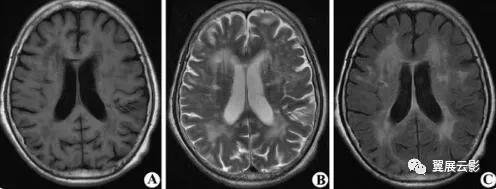

本病是一种在脑动脉硬化基础上发生的以进行性痴呆为临床特征的脑血管病,主要病因为各种原因引起的脑动脉硬化导致大脑半球深部白质区长穿支动脉透明变性,管壁中层变厚,弹力组织变性,导致半卵圆中心和脑室旁白质局限性或弥漫性脱髓鞘,本病常伴有双侧基底节区腔隙性梗死和脑萎缩,一般胼胝体及皮层下弓状纤维不受累,本病多见于老年人,起病隐匿,主要临床表现为进行性记忆力减退,智力减退,语言障碍等,亦可出现局部神经定位体征。

MRI扫描表现为脑室旁白质区或半卵圆中心片状长T1长T2异常信号,根据MRI表现分三型:1型脱髓鞘病灶局限于双侧额角旁或枕角旁白质区;2型脱髓鞘病灶散步于两侧侧脑室体及前后角周围,但病灶间相互融合;3型病灶发内继续扩大且相互融合,环绕双侧侧脑室周围。本病MRI上还可见双侧基底节区及半卵圆中心多发腔隙性梗死,2,3型病例可有脑萎缩表现。本病应注意描写脱髓鞘病灶的部位,形态及有无融合,同时还应注意描写有无多发腔隙性梗死及脑萎缩征象,本病应和多发性硬化相鉴别,本病脱髓鞘病灶一般不与脑室壁呈现垂直关系,一般胼胝体不受累,此两点有别于多发硬化。